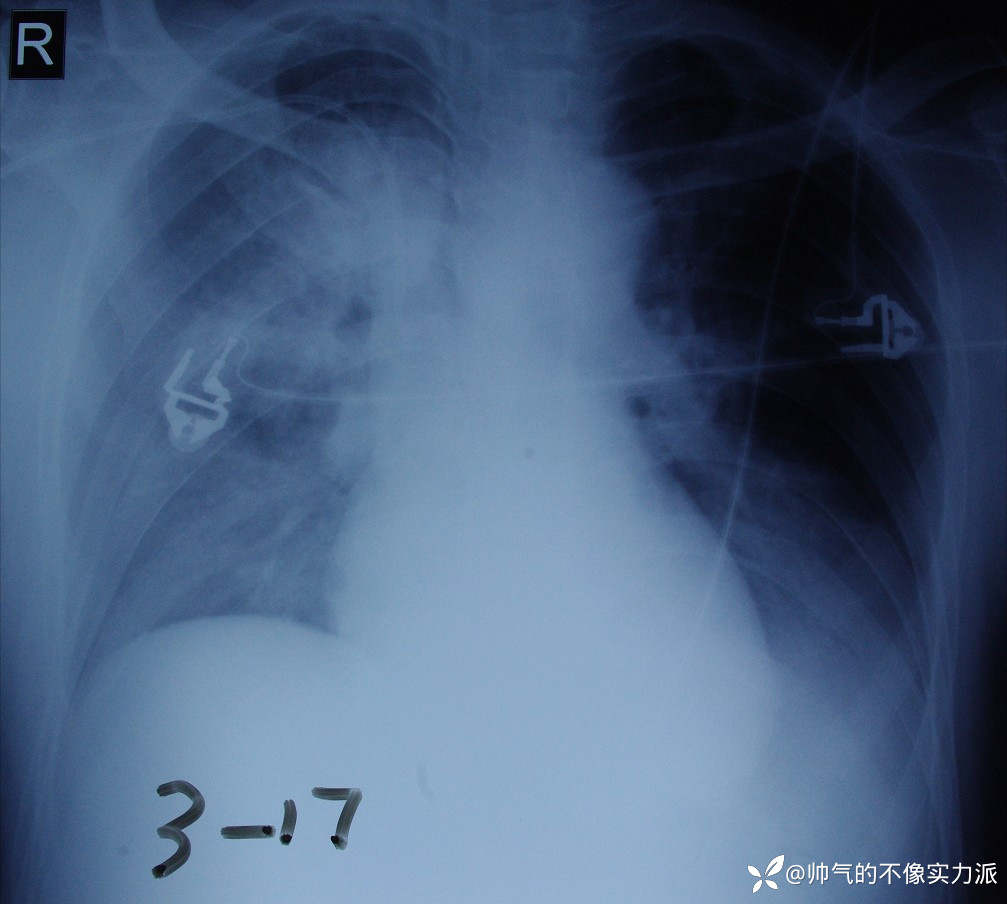

等我冲到科里,患者呼吸在30次/分以上,脉搏氧饱和度降到了72%。急诊床旁胸片几乎整个右肺全白了(图1)。

图1